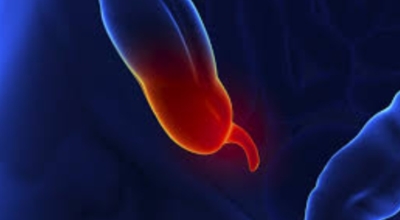

대장이 시작되는 부위를 맹장이라고 하며 그 끝부분에 약 5~10cm 정도의 길이로 꼬리처럼 달린 구조물을 충수 및 충수돌기라고 하는데, 흔하게 말하는 맹장염은 이 충수가 막히거나 눌려서 염증이 발생해 통증이 생기게 되는데 심할 경우 터지는 경우가 발생하기도 합니다.